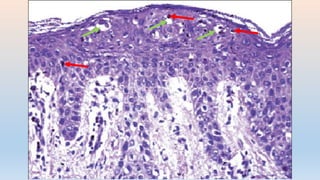

DERMATITIS FOTOALERGICA

• PREVALENCIA BAJA

• NO REACCION EN 1ERA EXPOSICION

• 24-48 HRS

• DOSIS PEQUEÑA

• ESPECTRO DE ACCION ALTO , INCLUYE UVA

• LESIONES ECCEMATOSAS

• PICOR

• TENDENSIA A EXTENDERSE

• HIPERSENSIBILIDAD RETARDADA (TIPO IV)

• DERMATITIS ESPONGIOTICA